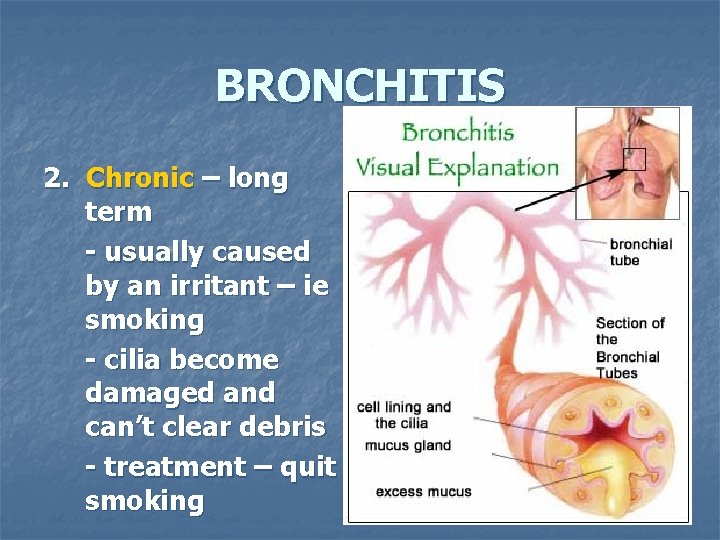

BRONCHITIS 2. Chronic – long term - usually caused by an irritant – ie smoking - cilia become damaged and can’t clear debris - treatment – quit smoking